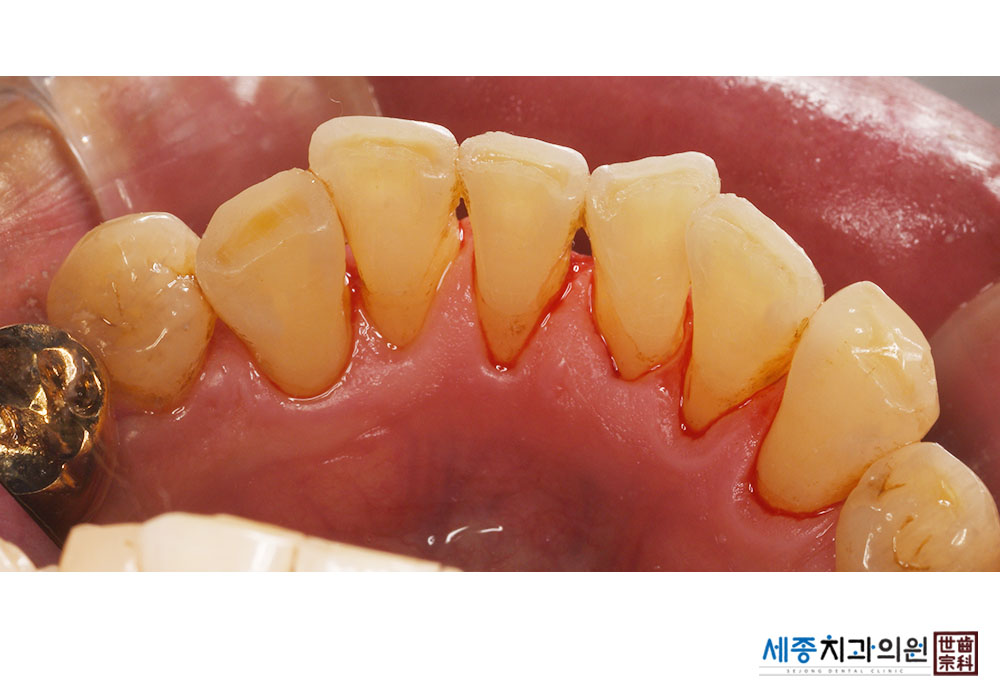

[스케일링] 치주질환 예방 스케일링

치료전 : 2021-11-04

치료후 : 2021-11-04

가글마취&저주파 스켈러를 사용한 스케일링